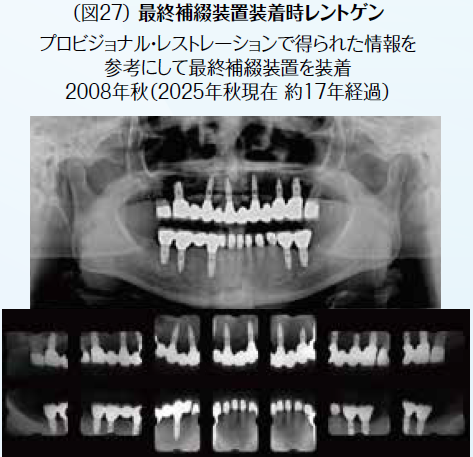

よって上顎は左右7を保存し、欠損部に関してはインプラントを用いたブリッジで修復。下顎は両側遊離端欠損部に関してはインプラントにて回復し、下顎前歯部に関しては歯冠修復によって咬合接触をコントロールすることを計画した。治療計画通り処置を行うことができ、メンテナンスに移行した。患者の都合で年近くリコールが途絶えたが、再初診が2025年5月で術後16年以上が経過。メンテナンス不足により天然歯はカリエスが進行し保存不可能になったが、インプラントの状態は良好な状態が維持され、口腔機能の維持が保たれている。歯科医として歯の保存に努めるのは当然のことだが、対極の立場に立ち、口腔内全体を治療するために何を優先すべきかを考えさせられるケースになった。

症例2はインプラントを用いた全顎的咬合再構成症例を提示した。術後10年以上経過し、その間このようなインプラント症例に対してデジタルを活用することで、より治療計画の遂行が確実になったと考える。症例2に似た症例でデジタルを活用した症例を提示する。今後のインプラント治療を含めた修復治療、矯正治療においてデジタルを活用する用途がますます増えてくると考える。(図15~図27)